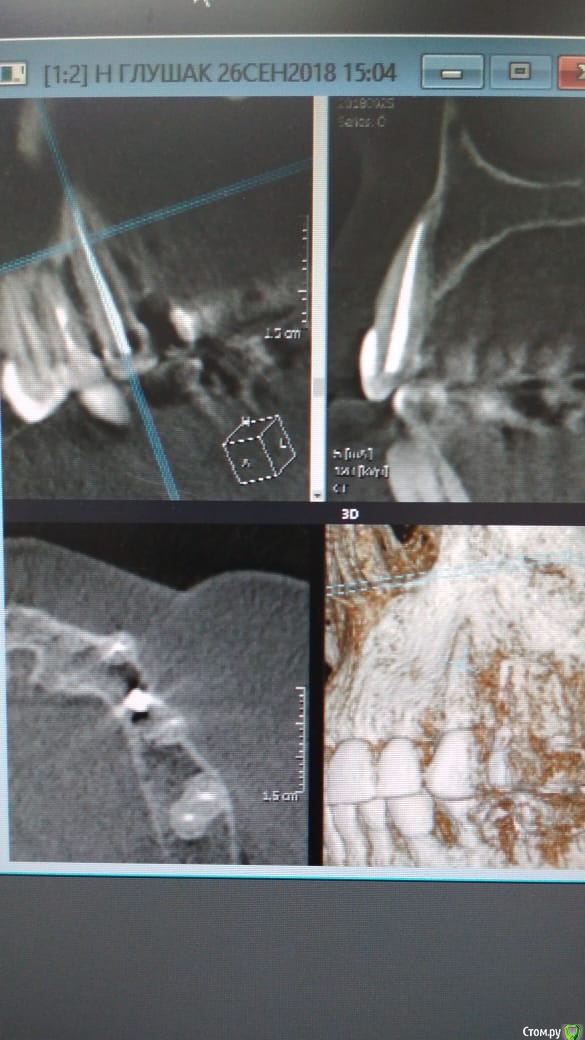

Alexandr_doc Опубликовано 26 сентября, 2018 Автор Поделиться Опубликовано 26 сентября, 2018 Прошу извинить за задержку. Прикладываю срезы со свежего КТ. Поступили предложения о хир удлинении, на мой взгляд это в данной ситуации очень рискованно. Ссылка на комментарий

kramer Опубликовано 26 сентября, 2018 Поделиться Опубликовано 26 сентября, 2018 Может, прозвучит банально, но нет смысла резцы вывести из окклюзии? По КТ плотный контакт с антагонистами Ссылка на комментарий

Alexandr_doc Опубликовано 26 сентября, 2018 Автор Поделиться Опубликовано 26 сентября, 2018 Я думаю в скором времени я буду вполне рассматривать варианты выведения зубов из окклюзии ( насколько это возможно ) или снятия коронок на некоторое время, например на день с колпачками из композита Ссылка на комментарий